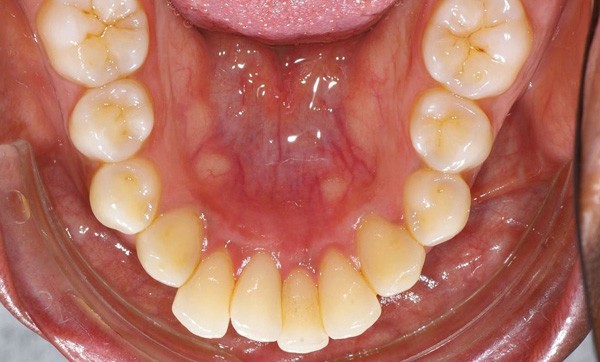

Le principal inconvénient de la génioplastie conventionnelle est son inesthétisme et son manque d’efficacité dans les cas nécessitant une forte correction. En effet, nombreux sont les patients qui retrouvent un contact bilabial imparfait suite à la génioplastie ou qui se plaignent de l’aspect peu naturel et inesthétique du « menton pointu de sorcière » et des décrochés osseux latéraux liés au trait d’ostéotomie trop peu étendu en arrière et interrompant le bord basilaire. C’est pour cette raison qu’en 2009, Albano Triaca introduit la technique du wing. En prolongeant à la manière des ailes d’un oiseau le trait d’ostéotomie, celui-ci vient mourir doucement sur le rebord postérieur mandibulaire. Témoin de la recherche constante vers une amélioration technique toujours plus fine et un résultat plus naturel, le wing permet le traitement des dysmorphoses mentonnières voire mandibulaires autorisant une plus grande amplitude et diversité de mouvements tridimensionnels.

Le wing se caractérise par l’extention en arrière de la génioplastie conventionnelle.

L’incision se fait dans le vestibule inférieur de 37 à 47 en passant par la ligne médiane. Le changement par rapport à la génioplastie classique est que le trait d’ostéotomie qui démarre en avant assez haut (8 à 10 mm sous les aprex incisifs) fait ensuite un virage en dessous du trou mentonnier et se poursuit en arrière parallèlement au bord inférieur mandibulaire jusqu’à l’angle (ou au moins jusqu’à l’aplomb de la deuxième molaire). Les insertions musculaires très fortes, présentes sur toute la partie antérieure et inférieure du bord mandibulaire, sont préservées et déplacées en bloc. Cela explique la plus grande efficacité clinique du wing par rapport à la génioplastie « standard ». Le volume osseux déplacé est plus important et le soutien des tissus est plus efficace et plus ample. La…